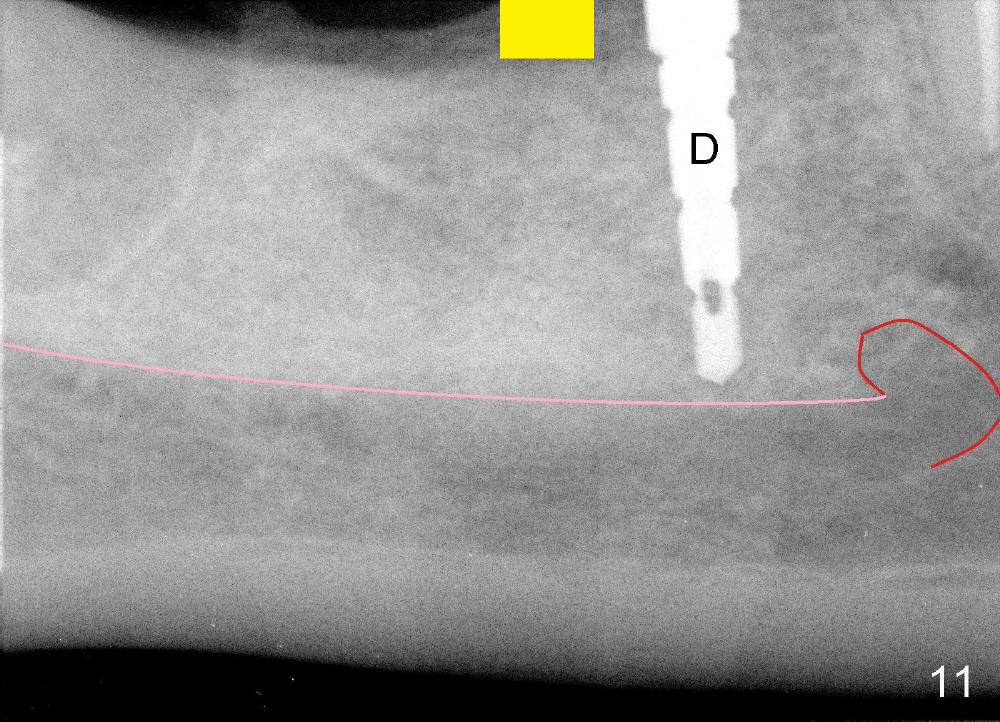

When the pilot drill is inserted into the initial osteotomy site for X-ray confirmation of its depth (Fig.7: D), the vertical block of the endo device (yellow rectangle) may be blocked due to the narrow divided edentulous space. The crown of the molar is shown, whereas the inferior alveolar nerve is not shown except a small portion in the left lower corner of Fig.7 (pink line). The depth of the further osteotomy (Fig.8: O) was chosen without accurate estimate. The integrity of the inferior alveolar canal (IAC) was violated, although the implant (I) was not placed that deep. The patient experienced transient postop pain, which was controlled by Medrol Dosepak. A correct way to prevent iatrogenic neuropathy in this situation is to remove the pilot drill, and place the endo device as deep as possible. The new X-ray should be able to reveal the relationship of the end of the osteotomy (shadow) to IAC. Measurement must be done using digital X-ray software over the new image to determine how deep osteotomy should be made (as shown in Fig.10). When an implant is placed (I in Fig.9: a second case as will be shown in Fig.10-12), the vertical block of the endo device can be placed on the implant. The sensor is placed deep into the lingual vestibule to show IAC in relation to the implant (Fig.8).